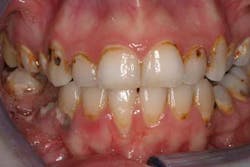

The deleterious effects of drugs such as methamphetamine, cocaine, Ecstasy, and marijuana have been reported in the literature and are well known in the dental community. Methamphetamine use is of particular concern to the dental community as the effects of this drug are devastating to the oral cavity, and patients with “Meth Mouth” are a challenge to treat (figure 1).

The signs and symptoms of use are well known and include rampant caries (especially smooth-surface and anterior interproximal lesions), fractured teeth from bruxism and clenching, and periodontal disease from oral hygiene neglect. (2) Unexplained and rapid deterioration of teeth is one of the hallmarks of drug use. Since these new drugs are most prevalent among young individuals who frequent the electronic dance music scene, asking about nightclub and dance festival attendance can be used as an indicator leading to further questions about potential use of these drugs (as long as this is done in a nonjudgmental manner).